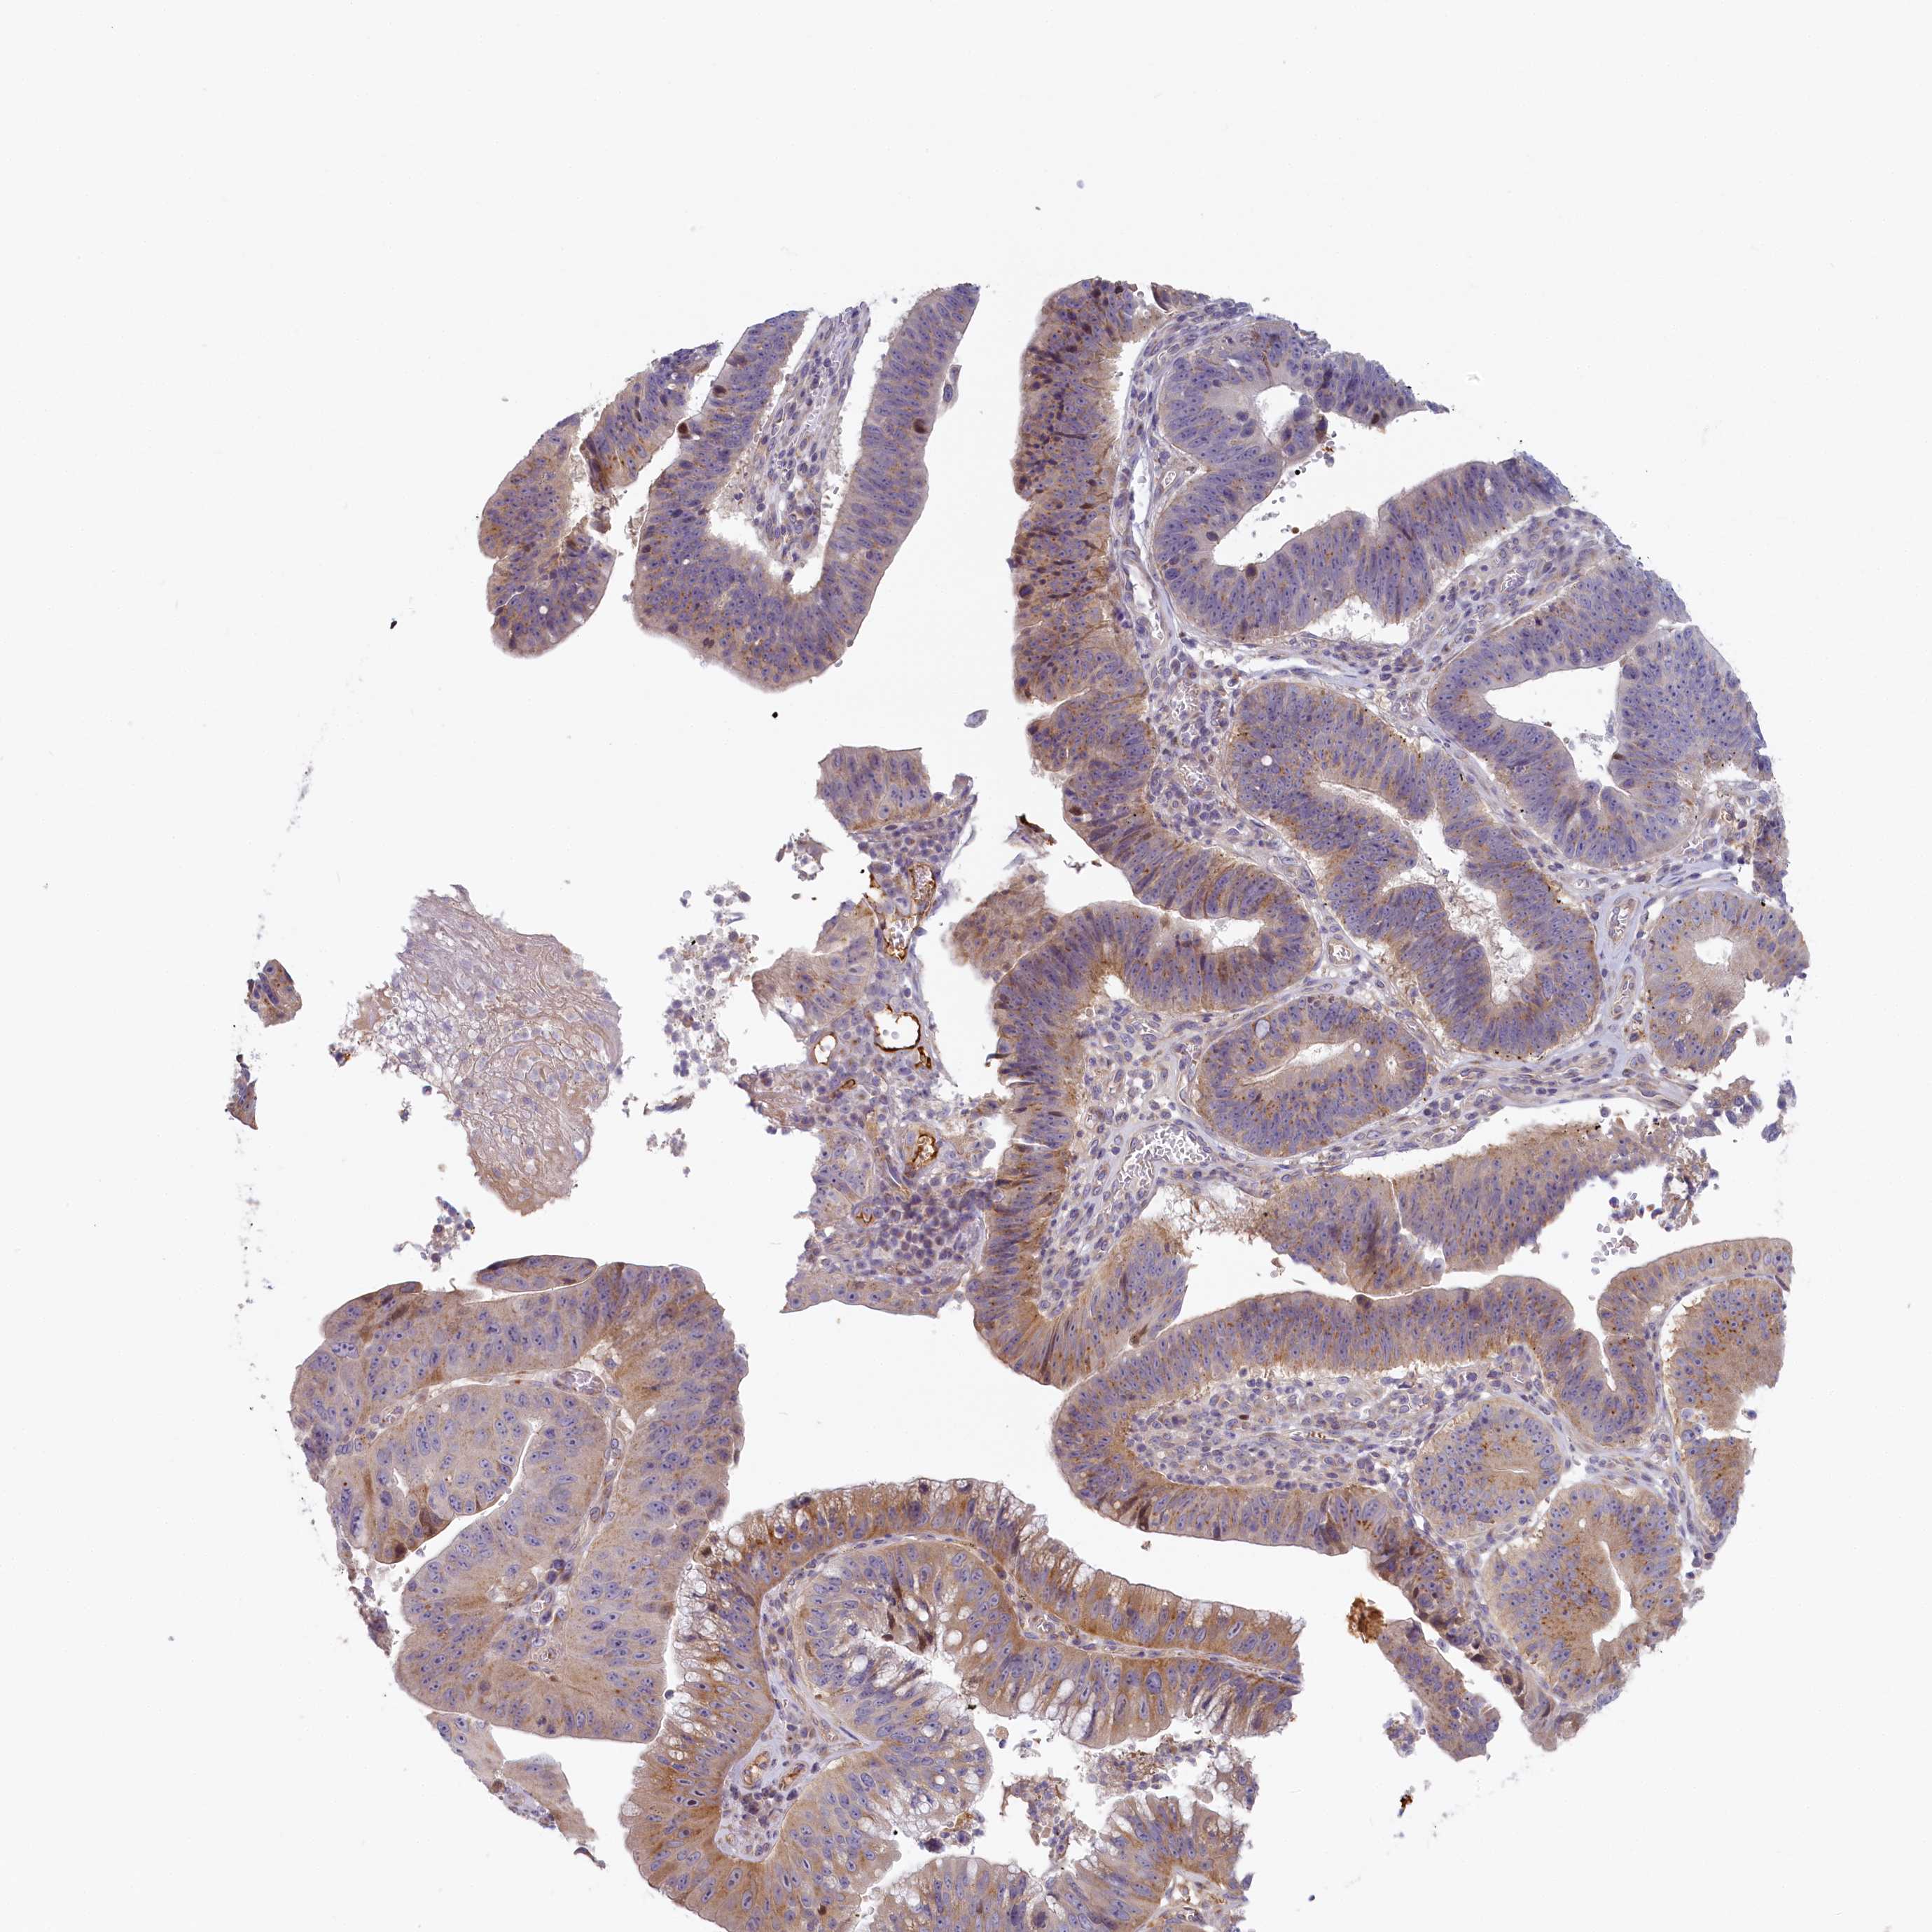

STOMACH CANCER - Protein expressioni

A mouse-over function shows sample information and annotation data. Click on an image to view it in a full screen mode. Samples can be filtered based on level of antibody staining by selecting one or several of the following categories: high, medium, low and not detected. The assay and annotation is described here.

Note that samples used for immunohistochemistry by the Human Protein Atlas do not correspond to samples in the TCGA dataset.

Antibody stainingi

Antibody staining in the annotated cell types in the current human tissue is reported as not detected, low, medium, or high, based on conventional immunohistochemistry profiling in selected tissues. This score is based on the combination of the staining intensity and fraction of stained cells.

Each image is clickable and will lead to virtual microscopy that enables deeper exploration of all samples and also displays staining intensity scores, fraction scores and subcellular localization as well as patient and tissue information for each sample.

Antibody HPA041019

Antibody HPA042033

Staining

High

Medium

Low

Not detected

Intensity

Strong

Moderate

Weak

Negative

Quantity

>75%

75%-25%

<25%

None

Location

Nuclear

Cytoplasmic/membranous

Cytoplasmic/membranous,nuclear

Adenocarcinoma, NOS